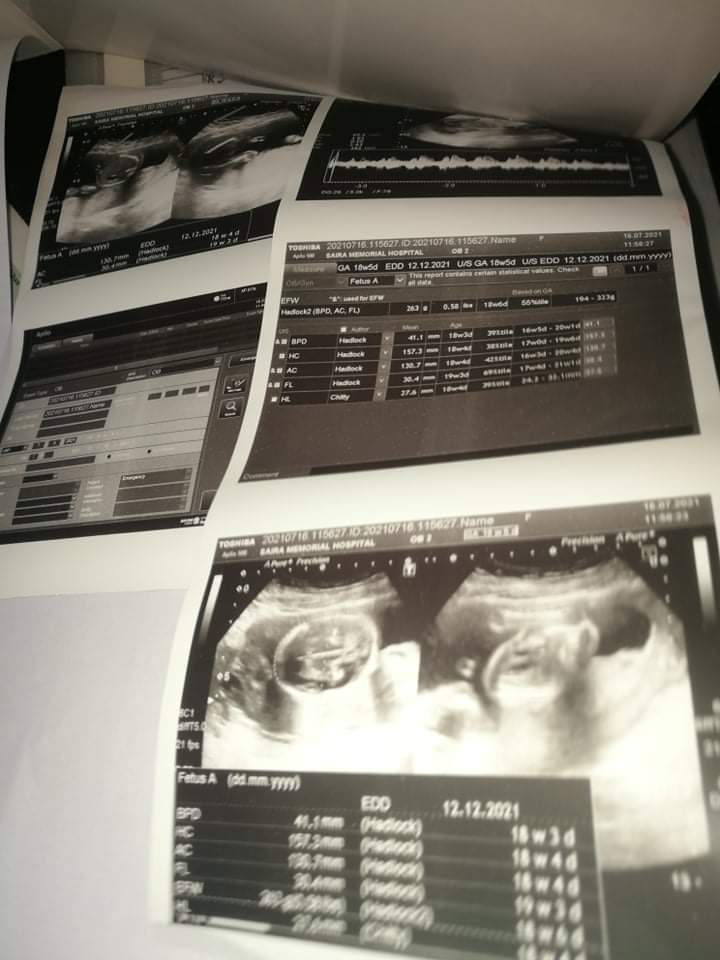

hi plz help me as im so depressed mri pregnancy ka 18th week he me start se private check up karwa rahi thi or medicine wagera or injection le rahi thi kal mene hospital up karwaya waha hi case karwana he . doc ne ultrasound kia or low lying placenta ka bataya jo ke pehle se hi araha tha takreban start se hi he me itni ahtyat kar rahi hun per ye abhi tak thek nahi hua .me reports or medicine bhi share karungi bata den k ye thek hoga ya nahi? or kya risks he isme mother or baby kya dono survive karlenge zyada hoga? kya Pakistan me aese cases successfully hain? mera hb bhi low he pehle 8 tha ab 10.7 he pehle wali doc ne 15 days or cac 1000 di thi per kal wali nahi bataya.k unki medicine ke sath ye continue karni he plz mujhe in sab chezon k leye bata den shukria

no need to worry its type 1 placenta previa , chance to migrate upward rescan at 32 wks..continues ur midication and fallowup regularly

Attach Photo here: